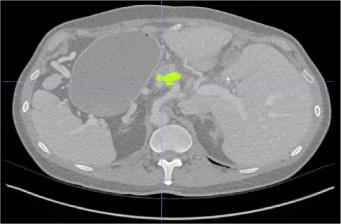

Creating large-scale and well-annotated datasets to train AI algorithms is crucial for automated tumor detection and localization. However, with limited resources, it is challenging to determine the best type of annotations when annotating massive amounts of unlabeled data. To address this issue, we focus on polyps in colonoscopy videos and pancreatic tumors in abdominal CT scans; both applications require significant effort and time for pixel-wise annotation due to the high dimensional nature of the data, involving either temporary or spatial dimensions. In this paper, we develop a new annotation strategy, termed Drag&Drop, which simplifies the annotation process to drag and drop. This annotation strategy is more efficient, particularly for temporal and volumetric imaging, than other types of weak annotations, such as per-pixel, bounding boxes, scribbles, ellipses, and points. Furthermore, to exploit our Drag&Drop annotations, we develop a novel weakly supervised learning method based on the watershed algorithm. Experimental results show that our method achieves better detection and localization performance than alternative weak annotations and, more importantly, achieves similar performance to that trained on detailed per-pixel annotations. Interestingly, we find that, with limited resources, allocating weak annotations from a diverse patient population can foster models more robust to unseen images than allocating per-pixel annotations for a small set of images. In summary, this research proposes an efficient annotation strategy for tumor detection and localization that is less accurate than per-pixel annotations but useful for creating large-scale datasets for screening tumors in various medical modalities.